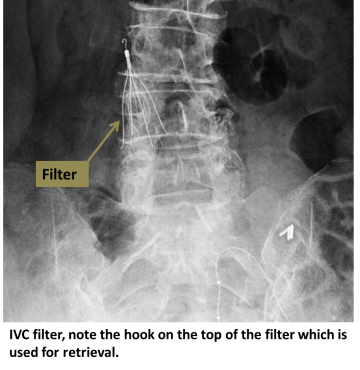

An interventional radiologist uses ultrasound to access the jugular vein at the neck, or the femoral vein at the groin. Contrast dye is injected to determine size and anatomy of the IVC. The filter is then deployed at the appropriate position in the IVC, where small hooks affix it to the wall.

Most IVC filters are retrievable. Once the filter is no longer needed, contact your interventional radiologist to arrange removal of the filter.